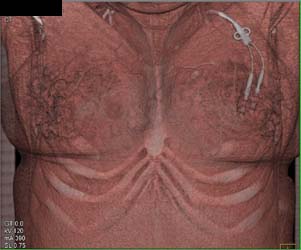

Lung Cancer Metastatic to Subcutaneous Tissue